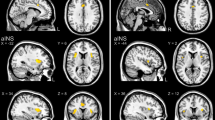

The conjunction analysis revealed that regions activated by somatic (Fig. 4a and Supplementary Table S2) and visceral stimulation (Fig. 4b and Supplementary Table S4) overlapped in a distributed set of brain regions (Fig. 4c and Supplementary Table S6), including midbrain, cerebellum, lentiform nucleus (putamen and pallidum), hypothalamus, thalamus (ventral lateral and ventral posterior lateral nucleus), parahippocampal gyrus/entorhinal cortex, insula (posterior, middle, and anterior parts), postcentral gyrus (including a medial cluster in primary somatosensory cortex (SI), and a ventral lateral cluster, including parietal/Rolandic operculum/secondary somatosensory cortex (SII)), adjacent inferior parietal lobule, superior temporal gyrus, and inferior frontal gyrus (ventrolateral prefrontal cortex (vlPFC)), lateral precentral gyrus, including primary motor cortex (MI) and premotor cortex, anterior and posterior midcingulate cortex (aMCC, pMCC) and adjacent medial frontal gyrus, and superior/middle frontal gyrus (dorsolateral prefrontal cortex (dlPFC)).

Parametric group-level maps of responses across participants and studies, controlling for interstudy differences. a The contrast of somatic stimulation versus baseline. Warm colors correspond to increased levels of activation and cool color deactivation (N = 76). b The contrast of visceral stimulation versus baseline (N = 89). c The conjunction of activation and deactivation maps for somatic and visceral stimulation (N = 165; the intersection of significant somatic and visceral results). d Contrasts of somatic (N = 76) and visceral pain (N = 89). In the top panel, effects are masked with the map of somatic pain > baseline for orange areas and visceral pain > baseline for yellow areas. Thus, the resulting maps show stimulus-related increases that are stronger for somatic (orange) or visceral (yellow). In these bottom panels, the difference map is masked with somatic pain < baseline for cyan areas and visceral pain < baseline for purple areas. Thus, the resulting maps show areas where stimulus-related deactivation occurs and is stronger in somatic pain (cyan), and deactivation occurs and is stronger in visceral pain (purple).

The conjunction analysis also revealed that regions deactivated by somatic (Fig. 4a and Supplementary Table S3) and visceral stimulation (Fig. 4b and Supplementary Table S5) overlapped in multiple brain regions (Fig. 4d and Supplementary Table S7), including thalamus (pulvinar), hippocampus, parahippocampal gyrus/perirhinal cortex, temporal pole, rostral middle/inferior temporal gyrus, occipital cortex and adjacent caudal middle and superior temporal gyrus, perigenual and subgenual anterior cingulate cortex (pACC, sACC) and adjacent medial, middle and superior frontal gyrus (vmPFC and dorsomedial prefrontal cortex (dmPFC)), lateral middle and superior frontal gyrus (dlPFC), PCC and adjacent precuneus, superior parietal lobule, left dorsal precentral gyrus (MI, premotor cortex), and left dorsal postcentral gyrus (SI).

Of the regions that showed significant activation (i.e., increased activity to somatic or visceral stimulation compared to baseline), regions demonstrating significantly stronger activation during somatic compared to visceral stimulation included midbrain, cerebellum, basal ganglia (caudate, lentiform nucleus, claustrum), thalamus (midline/medial dorsal/anterior nuclei), insula (posterior, middle, and anterior), inferior parietal lobule, postcentral gyrus/SI, parietal operculum/SII, temporoparietal junction, aMCC/pMCC, (pre)motor cortex, and middle frontal gyrus (dlPFC) (Supplementary Table S9 and Fig. 4a, b, e). Regions more strongly activated by visceral stimulation included thalamus (pulvinar), lentiform nucleus, amygdala, (caudal) parahippocampal gyrus, fusiform gyrus, occipital cortex (lingual gyrus, cuneus), precuneus/PCC, middle temporal gyrus, inferior and superior parietal lobule, and precentral/middle frontal gyrus (details in Supplementary Table S10 and Fig. 4a, b, e).

Of the regions that showed significant deactivation (i.e., decreased activity to somatic or visceral stimulation compared to baseline), regions demonstrating significantly stronger deactivation during somatic compared to visceral stimulation included rostral hippocampus/parahippocampal gyrus/entorhinal cortex, fusiform gyrus, temporal pole, middle and inferior temporal gyrus, occipital cortex (inferior & middle occipital gyrus, lingual gyrus, cuneus), pACC, sACC, vmPFC, orbitofrontal cortex (OFC) and dmPFC, PCC, precuneus, superior and inferior parietal lobule, vlPFC, and right dlPFC (Supplementary Table S11 and Fig. 4a, b, f). A more limited number of regions showed significantly stronger deactivation during visceral compared to somatic stimulation, including caudal hippocampus/parahippocampal gyrus and adjacent fusiform gyrus, caudate, right precentral/medial frontal gyrus, and right superior parietal lobule (Supplementary Table S12 and Fig. 4a, b, f).